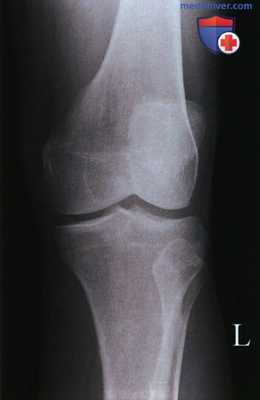

СНИМКИ КОЛЕННОГО СУСТАВА В ПРЯМОЙ ПРОЕКЦИИ

Назначение снимка. Рентгенографию коленного сустава производят во всех случаях заболеваний сустава и при травмах.

Укладки больного для выполнения снимков. Существует несколько вариантов укладки для выполнения этого снимка:

1. Чаще всего рентгенографию коленного сустава производят в прямой задней проекции. При этом больной лежит на спине, обе ноги вытянуты, сагиттальная плоскость стоп расположена перпендикулярно к плоскости стола. Кассету размером 18 х 24 см располагают в продольном положении. Проекция суставной щели, находящаяся при вытянутой ноге на 1,5—2 см ниже нижнего полюса надколенника, легко прощупываемого под кожей, соответствует средней линии кассеты. Пучок рентгеновского излучения направляют отвесно на центр кассеты (рис. 411).

Информативность снимка. На снимке коленного сустава в прямой задней проекции определяются дистальный метаэпифиз бедренной кости, медиальный и латеральный мыщелки бедра, между которыми располагается межмыщелковая ямка. Выше мыщелков определяются медиаль-ный и латеральный надмыщелки. На фоне дистального метаэпифиза бедренной кости виден надколенник. Проксимальный эпифиз большеберцовой кости представлен медиальным и латеральным мыщелками, между

которыми определяются медиальный и латеральный межмыщелковые бугорки. На латеральный отдел метаэпифиза большеберцовой кости частично накладывается головка малоберцовой кости. Между мыщелками бедренной и большеберцовой костей выявляется рентгеновская суставная щель коленного сустава в виде неравномерно изогнутой полосы просветления (рис. 415).

Информативность снимков коленного сустава как в задней прямой, так и в передней прямой проекциях одинаковая. В передней прямой проекции несколько лучше видна структура надколенника. Информативность одномоментных снимков коленных суставов в прямой задней проекции ниже, так как каждый из суставов при этом подвергается проекционным искажениям.